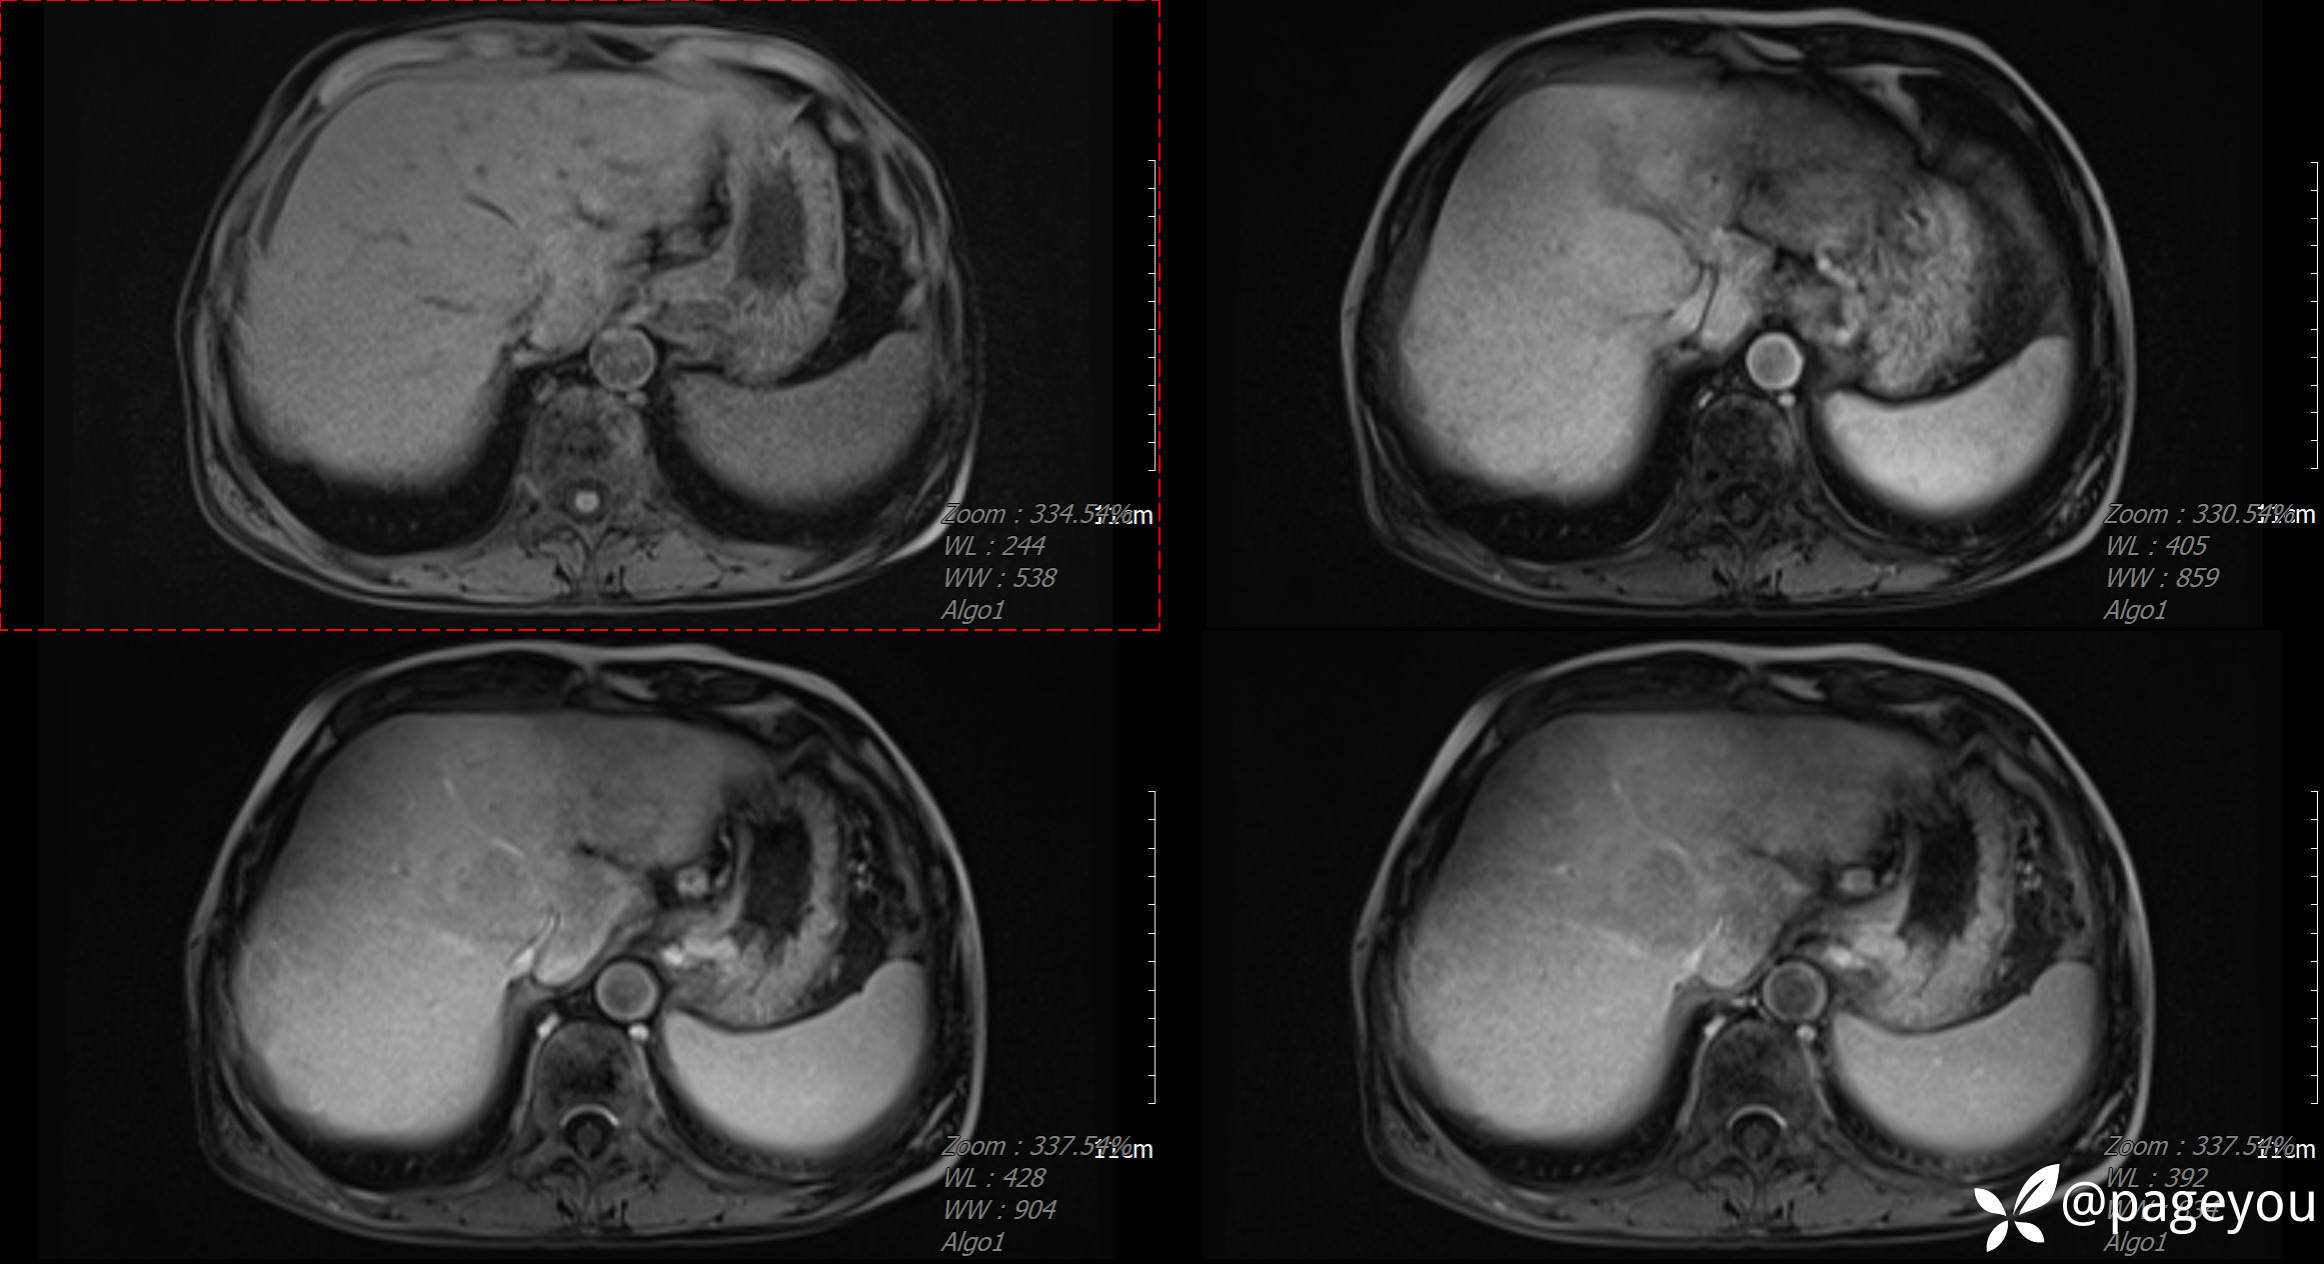

CT检查: